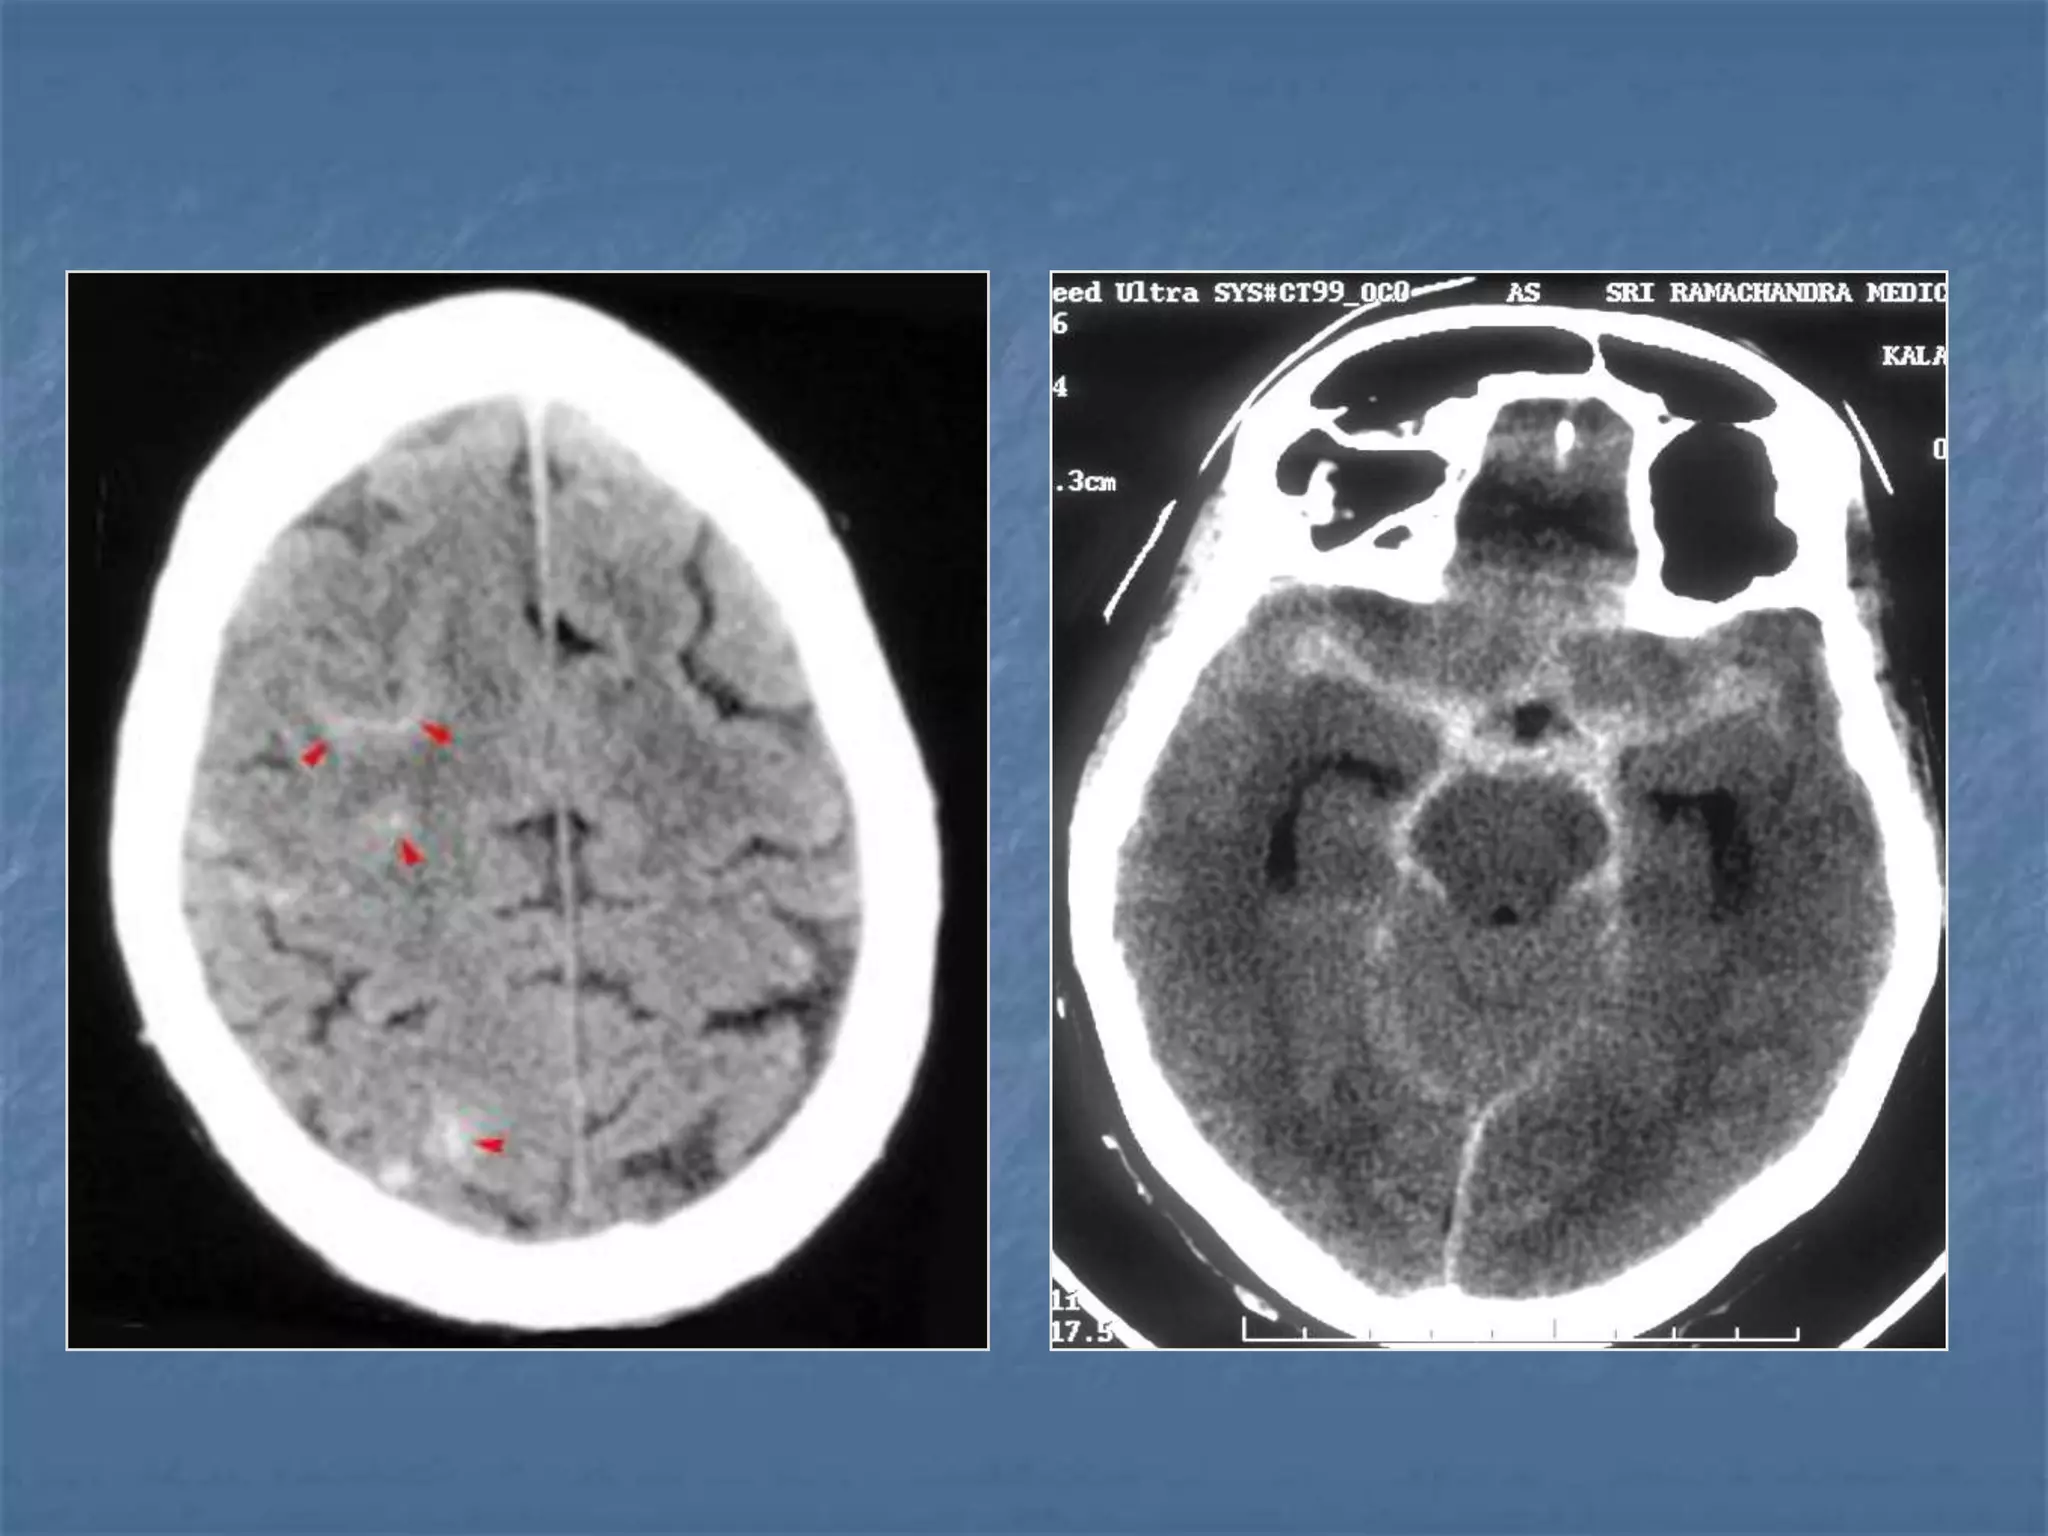

Epidural Abscess Subdural

Empyema

 Notice the rim enhancing

epdural fluid collection

(arrowheads)

).

Subdural Empyema

 Subdural empyema is usually due to

meningitis, sinusitis, trauma or prior surgery.

It is a neurosurgical emergency. Subdural

empyema leads to rapid clinical deterioration,

especially if it is due to sinusitis. On CT it

appears as an isodense or hypodense extra-

axial mass. It has a lentiform or crescentic

shape.

The margin of collection often enhances with

contrast material administration due to the

presence of granulation tissue or subjacent

cortical inflammation.

Extra-axial CNS Infection

 Extra-axial CNS infections can cause epidural

abscess or subdural empyema. Extra-axial CNS

infections account for 20-30% of CNS infections.

Fifty percent of extra-axial infections are

associated with sinusitis, usually frontal sinusitis.

The infection occurs by direct extension or septic

thrombophlebitis. Thirty percent of extra-axial

infections occur post-craniotomy. Finally, 10-15%

of extra-axial CNS infections are related to

meningitis. CT findings include a focal fluid

collection usually with an enhancing margin in a

subdural or epidural location.